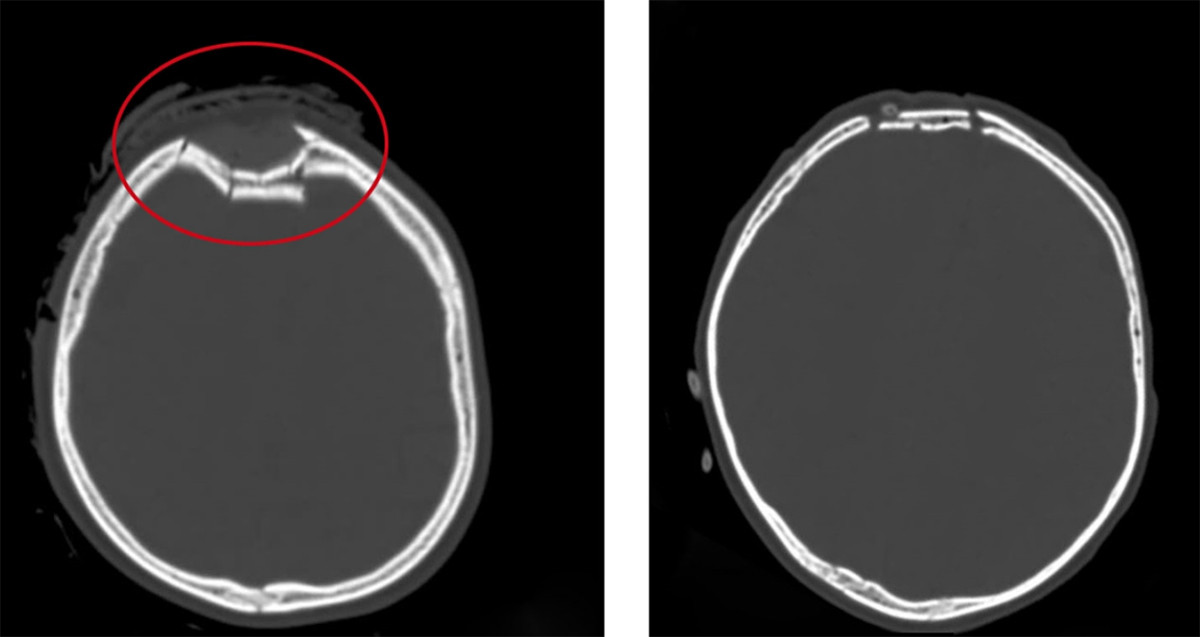

Hình ảnh vùng sọ não bị lún của trẻ trước và sau khi phẫu thuật (vùng khoanh tròn màu đỏ). (Ảnh: Bệnh viện Việt Nam - Thuỵ Điển Uông Bí)

Các bác sĩ khi thăm khám trên phim chụp CT.Scanner sọ não phát hiện, trẻ bị vỡ lún xương sọ trán phải, đụng dập tụ máu nhu mô não trán phải. Bệnh nhi được phẫu thuật nâng lún xương sọ, cầm máu và xử trí vết thương.